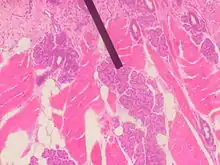

Von Ebner's glands, also called Ebner's glands or gustatory glands, are exocrine glands found in the mouth. More specifically, they are serous salivary glands which reside adjacent to the moats surrounding the circumvallate and foliate papillae just anterior to the posterior third of the tongue, anterior to the terminal sulcus.

Von Ebner's glands secrete lingual lipase,[1] beginning the process of lipid hydrolysis in the mouth. These glands empty their serous secretion into the base of the moats around the foliate and circumvallate papillae. This secretion presumably flushes material from the mouth to enable the taste buds to respond rapidly to changing stimuli.

Von Ebner's glands are innervated by cranial nerve IX, the glossopharyngeal nerve.